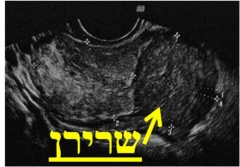

בדיקת האולטרה-סאונד היא בדיקה זמינה ופשוטה. הבדיקה מאפשרת לקבל פרטים על מבנה וגודל הרחם, מיקום וגודל השרירנים, רירית הרחם, אספקת הדם, מראה השחלות, ועוד. אם וכאשר מודגמים שרירנים על מסך הסריקה, מקובל לתעד זאת ולמדוד את גודלם. התמונות מודפסות ישירות ממסך המכשיר. ניתן לראות בהן צללים המייצגים שרירנים, וסמני מחשב המגדירים את מידותיהם.

| תרשים מספר 2: תמונות מבדיקות אולטרה-סאונד המדגימות שרירני רחם | ||

במרבית המקרים, לא ניתן לקבל החלטות טיפוליות על סמך תמונות האולטרה-סאונד בלבד. יש לבצע תיעוד נלווה של הממצא במילים ובאיור, המתאר את מספר השרירנים וגודלם ואת מיקומם ביחס לדופן הרחם, ולסכם את תוצאות הבדיקה בצורה מדויקת. הסיכום, הנעשה על ידי הרופא המבצע, משמש לקבלת ההחלטה אודות הטיפול המתאים ביותר לצורך ולרצון האשה.